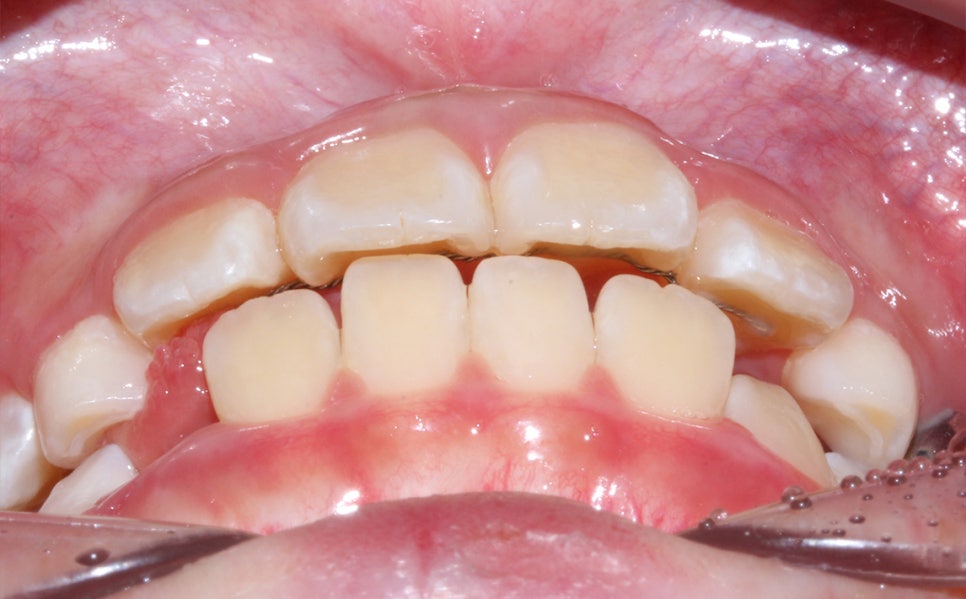

환자분의 상태를 살펴보면

치아가 날 공간이 부족하거나 치아가 나오는 방향에서

앞니가 앞으로 나오고 다른 치아가 기울어지면서

거꾸로 물리는 현상이 발생한 걸로 보여요.

상하악 Clippy-C (클리피씨) 전체 교정

구치부 반대교합은 통상적으로 비발치 교정일 경우에는

1년~1년 반 정도 교정 기간을 생각하고 있었어요-:D

<24개월 교정 완료 모습>

전체적으로 치아가 크게 개선이 되었어요.